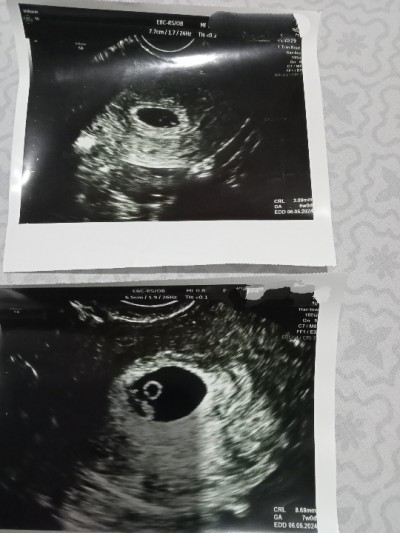

Kızlar merhaba keseye göre Cinsiyet tahmini yapıldığını gördüm bana da bakarmisnz bilenler şuan 9 +1 ama 6 hafta ve7. Hafta ultrasonu ekliyorum öncelikle sağlıklı olması tabi ama yine de merak ettim

Muz gibi keseye erkek yuvarlak keseye kız diyorlar benimki yuvarlaktı kız oldu ama böyle şeylere inanmiyorum

Keseye gore kiz bebek ama ne kadar dogru bilinmez